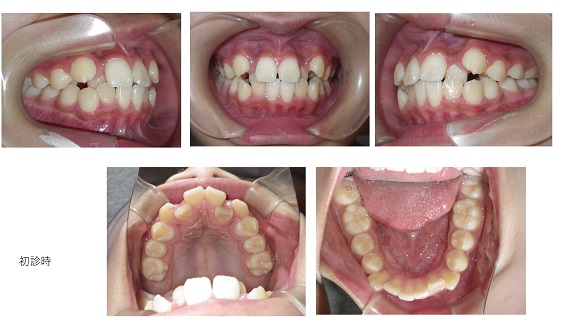

矯正症例109 AngleⅠ級上下顎前突、能代市、北秋田市、大館市、秋田市

初診時29歳女性、抜歯部位:上下顎左右4番、治療期間3年8か月、来院回数62回 、治療費総額1,238,000(税込み)向かって左が初診時、右が動的治療終了時の正貌写真です。治療前後で唇の形が大きく変...